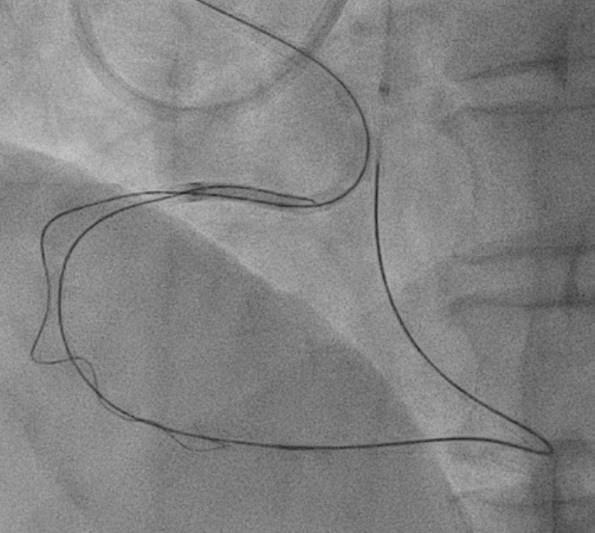

The strategy we plan was antegrade preparation and early retrogradly approach, due to challenging antegrade approach and also distal bifurcation1.XTA+Caravel microcatheter for antegrade preparation, failed advancement in mRCA2.retrograde with suoh03, but could not advance caravel and cosair pro microcatheters through septal channel3.extension catheter use, and balloon dilation for septal channel with low pressure4.caravel could enter dRCA, distal injection5.retrograde wire escalation for calcified CTO: Gaia2, Gaia3, Conquest pro6.kissing wire technique within dRCA7.both side MC could not pass the CTO, despite both side extension catheter use(img: step01)8.intracoronary tip-in, with retrograde wire anchored within AL1(img: step02)9.still failed advancing both side MC10.retrograde balloon dilation, sequentially from distal to middle RCA(img: step03)11.successful antegrade wiring to PL12.lesion preparation and drug-eluting stent placement13.good final angiography results